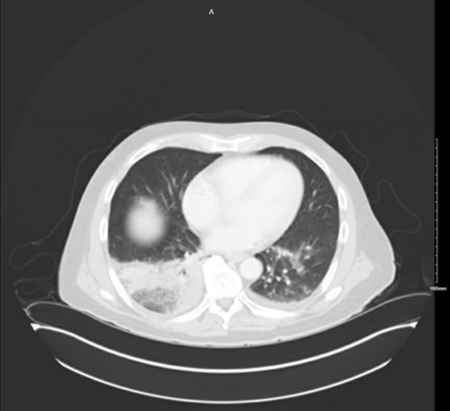

CT abdomen

Test

To evaluate for lobar infiltrate. If infiltrate is absent, but clinical suspicion remains, laboratory tests should be ordered.

[Figure caption and citation for the preceding image starts]: The superior aspect of a CT abdomen with contrast showing a right lower lobe, dense, lobar infiltrate consistent with Legionnaires' disease causing pneumonia with a small left pleural effusionFrom the personal collection of Dr Forest W Arnold; used with permission [Citation ends].

Result

Legionnaires' disease: lobar infiltrate; Pontiac fever: normal